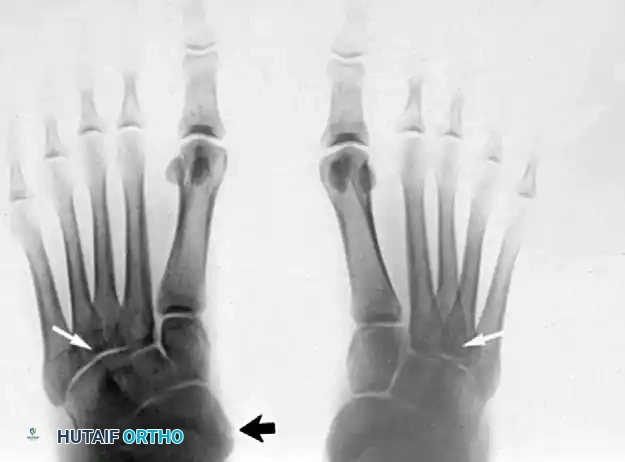

Insufficiency of the posterior tibial tendon secondary to an accessory navicular presents unique biomechanical problems. The presence of an accessory navicular alters the insertion vector of the PTT, reducing its mechanical advantage and predisposing the tendon to tendinosis and eventual rupture.

It would seem reasonable that if unilateral pes planus develops in a "prehallux foot," simply excising the accessory navicular and advancing the posterior tibial tendon should suffice. This is true provided the deformity is not severe and the opposite foot has a cornuate or accessory navicular but no pes planus.

However, this is most often not the case in advanced pathology. In a skeletally mature foot, unilateral pes planus with a plantar-flexed talus secondary to PTT insufficiency associated with a prehallux foot implies abnormal insertion and function of the PTT.